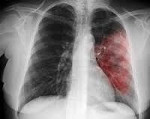

Если врач предполагает пневмонию, то диагноз следует подтвердить флюорографией, которая покажет степень инфекционного поражения легких. Для идентификации патогенного микроорганизма собирают и исследуют образцы мокроты. В целях уточнения диагноза также делают анализы крови.